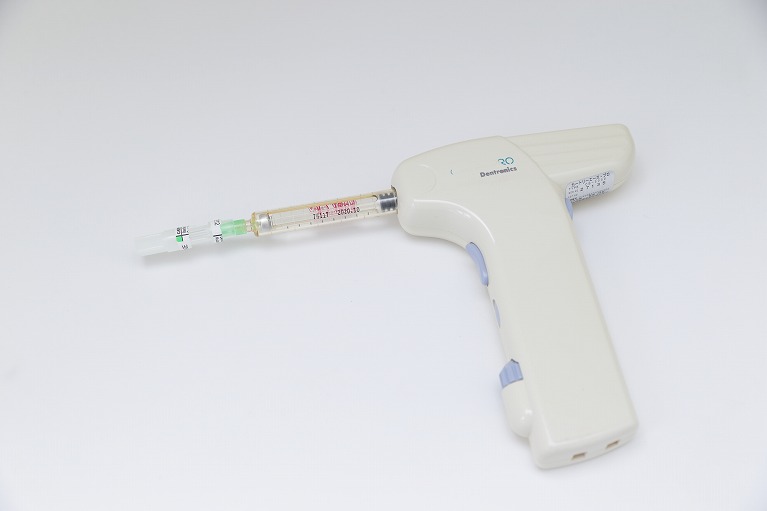

また、治療のあらゆる場面で痛みが出る可能性を考慮し、それにきめ細かく対応した治療を行っています。麻酔が効いて治療自体は痛くなくても、麻酔注射が痛いということもあると思います。そのため、いそむら歯科医院では細い注射針を使ってチクっとする痛みも軽減し、注射針を刺す際には解剖学的に痛みの少ない場所に行い、電動麻酔器でゆっくり注入していくことで圧迫による痛みも抑えています。

取り組み1.電動麻酔による注射で痛みも軽減しています

麻酔は治療中の痛みを取り除くためのものですが、以前は麻酔注射が痛いということが起こっていました。麻酔注射の痛みは、表面麻酔や細い針の使用、解剖学的に痛みの少ないポイントの見極め、薬剤の注入スピードのコントロールなどによって解消できるようになっています。

麻酔は治療中の痛みを取り除くためのものですが、以前は麻酔注射が痛いということが起こっていました。麻酔注射の痛みは、表面麻酔や細い針の使用、解剖学的に痛みの少ないポイントの見極め、薬剤の注入スピードのコントロールなどによって解消できるようになっています。